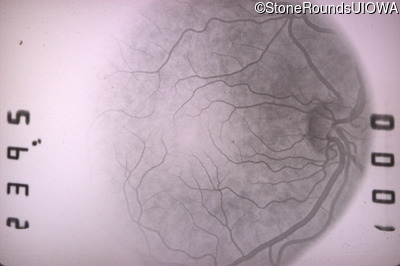

Fluorescein Angiography - Right - 20/25 +2 sc

Exemplar